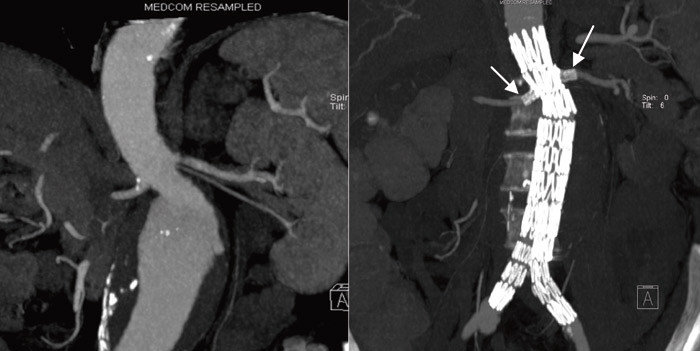

Ved åpen operasjon benyttes generell anestesi og det settes inn et rett eller bifurkert polyesterfibertransplantat (fig 1). Endovaskulær operasjon utføres transfemoralt og som oftest i regional anestesi (epidural). Prosedyren gjøres under gjennomlysning med kontrast, og vanligvis vil et bifurkert stentgraft med beinforlengelser benyttes. Stentgraftet holdes på plass av mothaker og den radiære kraften i metallskjelettet. Aortouniiliakale stentgraft benyttes bl.a. dersom det kun er tilgang via den ene sides iliakalkar, ved aortoiliakale aneurismer og ofte ved rumperte abdominale aortaaneurismer. Kontralaterale sides iliakalkar stenges da med en plugg og en femorofemoral overkrysningsbypass anlegges for å forsørge sirkulasjon i denne underekstremiteten.

Endovaskulær behandling kommer ikke til å erstatte åpen operasjon, siden mange aneurismer har en anatomi uegnet for stentgraft. Den største begrensningen vil være en for kort hals (avstanden fra nyrearteriene til starten på aneurismet). Flere setter inn standard stentgraft på korte aneurismehalser, med økt risiko for endolekkasje. For å øke andelen aneurismer som kan behandles endovaskulært er det blant annet utviklet individuelt tilpassede fenestrerte transplantat for ellers uegnede halser. Stentgraftet kan festes mer proksimalt ved å lage vinduer (fenestre) i stentgraftet for ett eller flere av de viscerale karene. Som oftest sikres plasseringen ved å sette stenter gjennom vinduene og inn i de viscerale arteriene (fig 2). Dette setter større krav til planlegging og utførelse og er atskillig mer kostbart enn standard stentgraft. Rapporterte korttidsresultater er gode, men det foreligger ingen randomiserte studier.